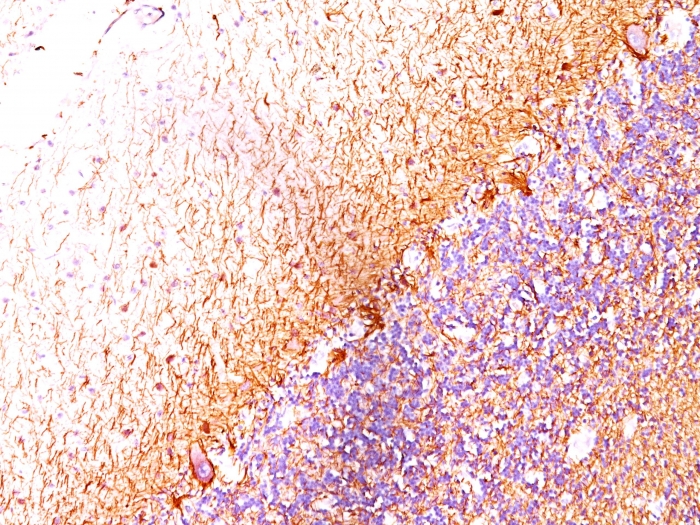

IHC-P analysis of cerebellum tissue using GTX34903 NF-L antibody [SPM204].